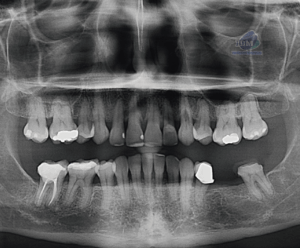

Figura 5: Vista panorámica postoperatoria 14 meses después